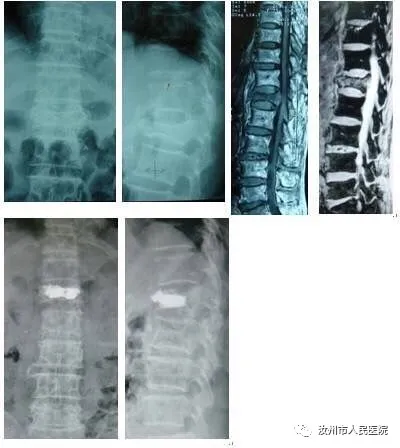

胸腰椎骨折多应用椎体成型技术。

只有0.5cm切口。术后第二天即可下床活动,减少卧床并发症。

而保守治疗多需卧床两到三个月,多数人不能配合,导致椎体压缩,后凸畸形,长期腰痛,给患者造成巨大痛苦。